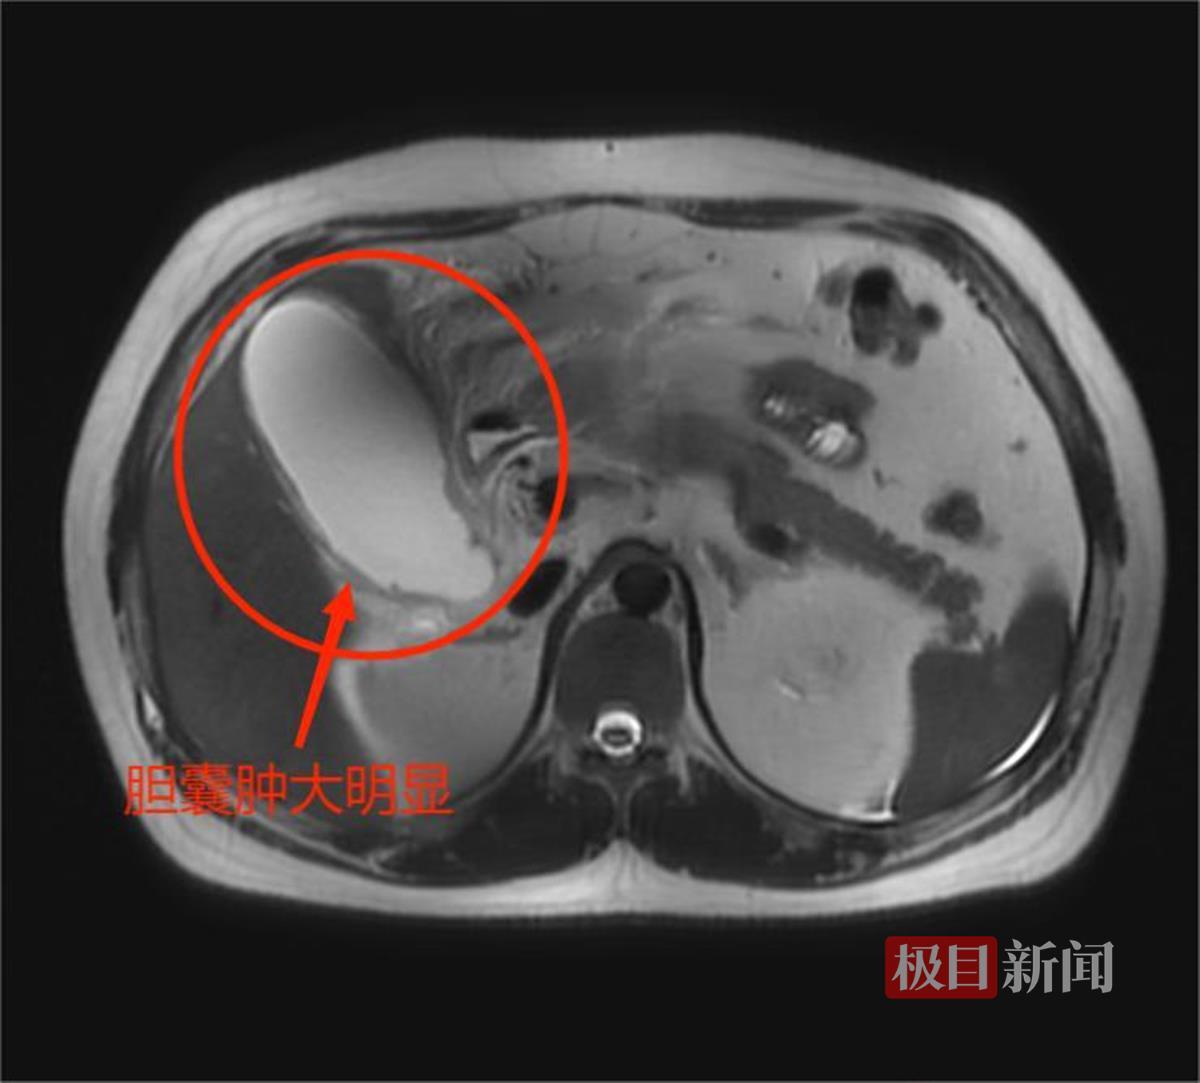

通过检查医生判断,小王的腹痛是由急性胆囊炎引起的,而磁共振结果显示,他的胆囊已经肿大到了12.7厘米,足足接近正常人胆囊的2倍大小(正常为5至8厘米),同时还伴有局部的腹膜炎。而此时的小王也已经开始出现全身感染的症状,高烧到了38.6℃,如果不马上进行治疗,极有可能造成感染性休克,随时危及生命。

磁共振下小王的胆囊(武汉市普仁医院供图)